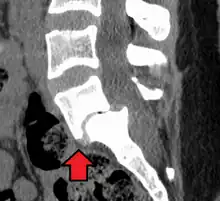

Anterolisthesis L5/S1

Anterolisthesis L5/S1. Blue arrow normal pars interarticularis. Red arrow is a break in pars interarticularis